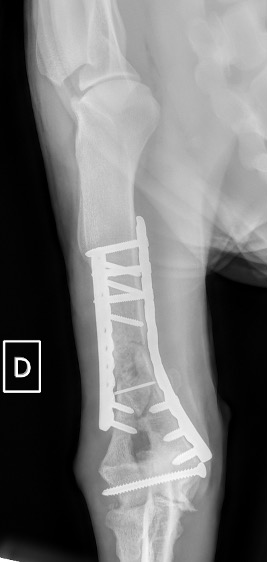

Exemple 1 :

Figure 1 : Pré-op

Figure 2 : Post-Op Immédiat

Figure 3 : Post-Op 1 Mois

Figure 3 : Post-Op 2 Mois